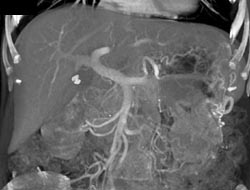

Chronic Pancreatitis